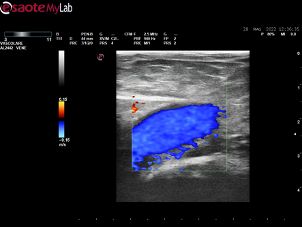

Svolgo attività quotidiana di diagnostica vascolare non invasiva, di cura delle arteriopatie e di tutte le patologie venose: varici, trombosi venose profonde acute, sindrome post-trombotica, ulcere venose e/o linfatiche, edemi degli arti inferiori, ulcere croniche.

• Ecocolordoppler vascolare

120 €